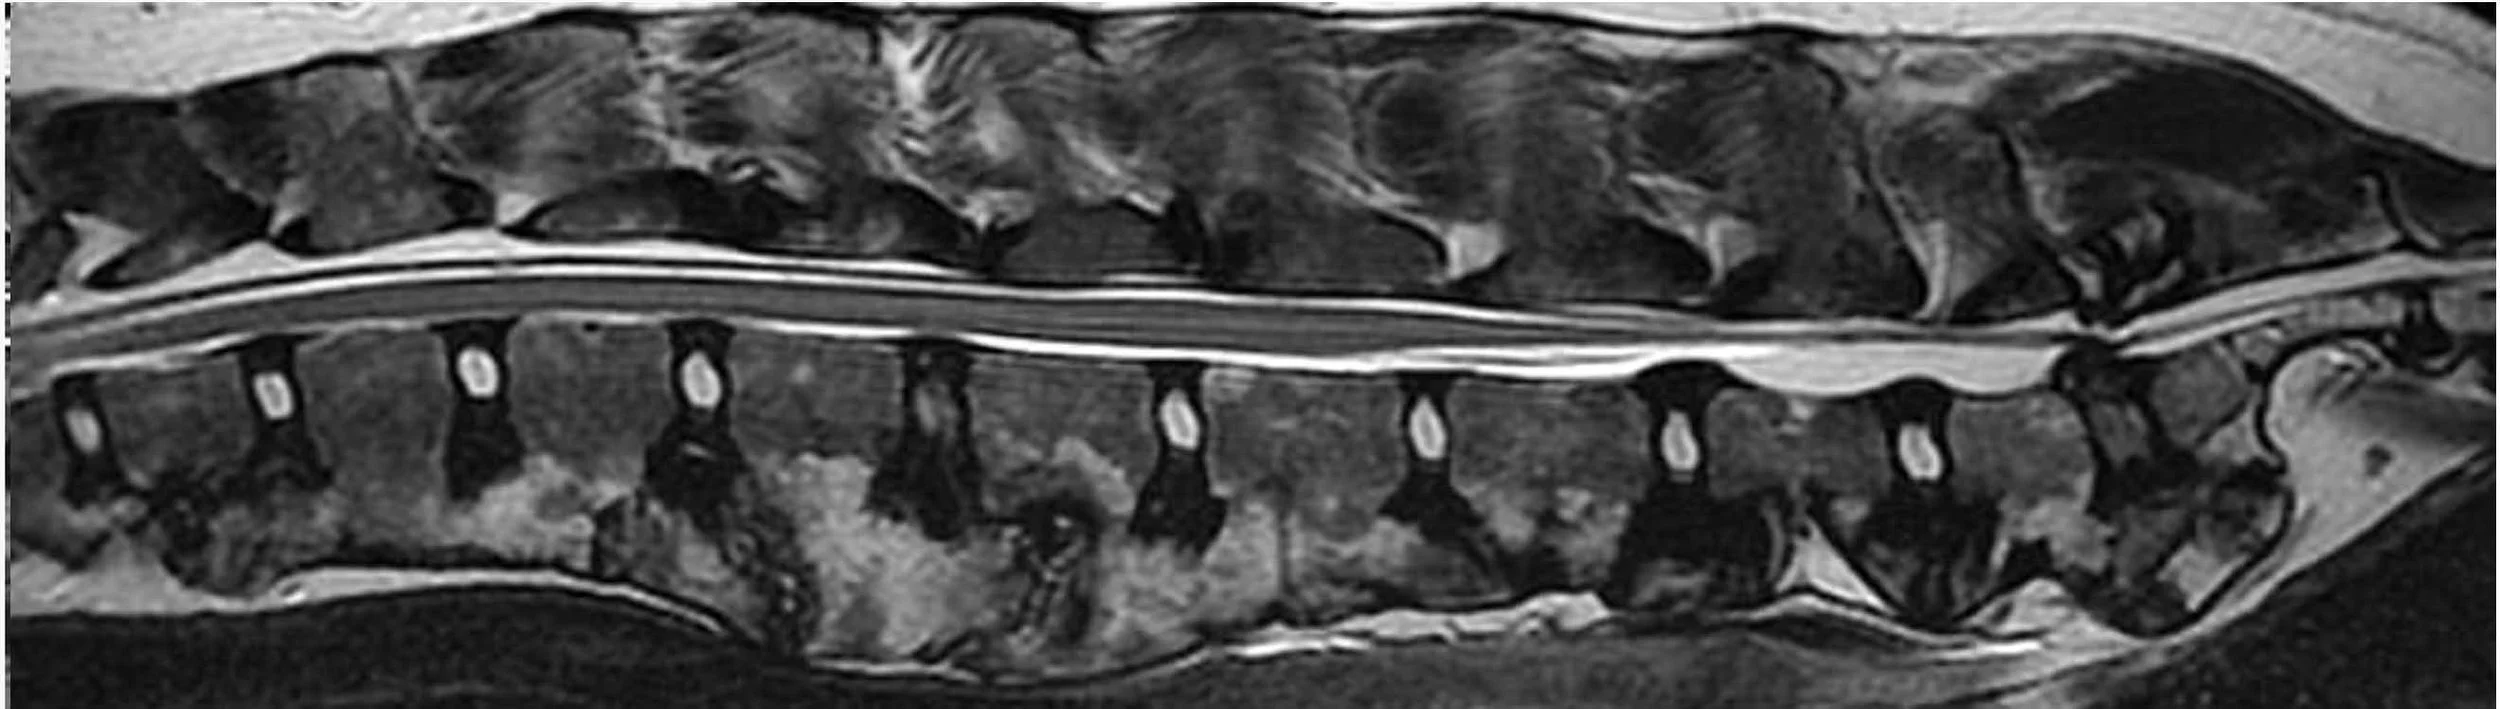

Spinal Injury

Spinal injury refers to damage to the bones, discs, or nerves of the spine caused by trauma or excessive force. In large, powerful breeds such as the Cane Corso, spinal injuries most commonly occur due to falls, uncontrolled jumping, collisions, or high-impact activity.

Injuries can range from mild soft tissue damage to more serious trauma affecting spinal stability or nerve function.

• Imaging such as X-rays, CT, or MRI where indicated